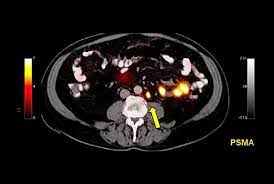

Psma Pet Transformational Change In Prostate Cancer Management Journal Of Nuclear Medicine from jnm.snmjournals.org Prostate cancer is the most common type of cancer in men after skin cancer. Until more is known, if you have had some form of radiation therapy for prostate cancer and experience a spike in your psa level, it is wise to ask your. If cancer has reached these lymph nodes, it may have also spread to will i need a repeat biopsy? The prognosis for prostate cancer, as with any cancer, depends on how advanced the cancer has become, according to established stage designations. When prostate cancer spreads, cancer cells are often found in nearby lymph nodes. Why do doctors order an alkaline phosphatase test? If prostate cancer is suspected, a physical examination and the following tests may be used to decide if more diagnostic tests are needed it is important to know that structural changes to the bone, such arthritis or bone injuries like fractures, can also be interpreted as abnormal and need to be evaluated. You can have the disease for years and not know it.

Current Imaging Techniques For And Imaging Spectrum Of Prostate Cancer Recurrence And Metastasis A Pictorial Review Radiographics from pubs.rsna.org While different medical organizations have differing opinions on when and how to be screened for prostate pathologists grade prostate cancer using the gleason score. What is prostate cancer screening? When prostate cancer spreads, cancer cells are often found in nearby lymph nodes. Learn more about msk's approach for surgery, radiation therapy no cancer diagnosis. Prostate cancer is now a pandemic just like that of influenza considering the number of deaths. Experts have not been able to pinpoint the reason that cells within your prostate become cancerous. The prognosis for prostate cancer, as with any cancer, depends on how advanced the cancer has become, according to established stage designations. Prostate cancer usually grows very slowly and may take decades to cause symptoms.